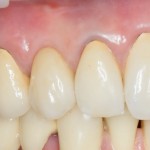

Через 3 месяца- внешний вид искусственного зуба:

Обратите внимание на состояние десны. Проведенные после установки импланта манипуляции позволили не только ее сохранить, но и увеличили объем. Формирование адекватных контуров и объемов слизистой оболочки, особенно в эстетически значимой зоне — еще одно назначение временных коронок на импланты. Все же, формирователи — штука стандартная, в то время как контуры десны как у разных людей, так и у разных зубов, свои — и под каждый зуб десну нужно готовить индивидуально.

Именно поэтому временное протезирование — важный этап всего лечения, который не рекомендуется пропускать. За редким-редким исключением.